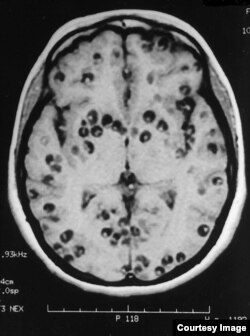

به گزارش سازمان بهداشت جهانی، چیزی بین ۲.۵ تا ۸.۳ میلیون نفر در سراسر جهان به عارضه‌ای به نام نوروسیستی‌سرکوزیس مبتلا هستند. این بیماری زمانی رخ می‌دهد که بخشی از لاروهای گونه‌ای از انگل به نام Taenia solium وارد مغز می‌شوند و کیست‌های کوچکی را در بافت مغزی ایجاد می‌کنند. این انگل را بیشتر به نام کرم نواری می‌شناسیم.

نوروسیستی سرکوزیس رایج‌ترین بیماری انگلی است که سیستم عصبی مرکزی را تحت‌تأثیر قرار می‌دهد

سازمان بهداشت جهانی اعلام کرده است که بیش از ۳۰ درصد از موارد وقوع حملهٔ صرع در کشورهایی که این حملات در آن شیوع دارد، نتیجهٔ ابتلا به این بیماری است و عمدهٔ مبتلایان را شهروندان کشورهای درحال‌توسعه تشکیل می‌دهند که با شرایط بهداشتی ضعیفی دست‌وپنجه نرم می‌کنند.

در عمدهٔ موارد این لاروها مشکل چندانی برای فرد ایجاد نمی‌کنند و می‌توانند چند سالی در مغز خانه کنند. عمدهٔ اثر آن‌ها در این دوره این است که آشیانه یا کیست‌های شفافی را در مغز ایجاد می‌کنند که چیزی در حدود یک سانتی‌متر قطر دارد و باز هم در اغلب موارد مشکل‌ساز نیستند. این بچه‌انگل‌ها توان رشد در مغز ندارند و تمام دوران اقامت‌شان در مغز به شکل لارو است.